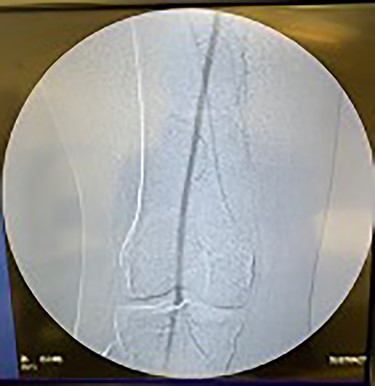

Catheter arteriogram results showed significant occlusion of the left iliac artery (Figs 3 and 4), the right iliac artery (Fig. 1), as well as the distal abdominal aorta (Fig. 2). There were numerous collateral vessels noted, indicating the presence of long-standing proximal stenosis (Fig. 1). The decision was made to use angioplasty to help widen the areas of stenosis. An 8 mm × 40 mm Passeo balloon was advanced from the right femoral artery into the left iliac artery (Fig. 7) and insufflated to 6 mmHg (Fig. 6). The balloon was allowed to remain expanded for 1 min and then was deflated. Next, the distal aorta was repaired in a similar fashion. The balloon was advanced into the distal aorta from the right femoral access and insufflated to 12 mmHg (Fig. 8). The balloon was allowed to remain expanded for 90 s.

Fluoroscopy of right iliac artery showing vast collateral vascular formation, indicating long-standing proximal obstruction.